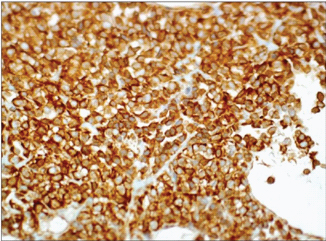

A 39-year-old female patient presented with complaints of abdominal discomfort & vague pain since 2 months, following weakness in lower limb and loss of weight. On investigation, the haematological profile, renal function test and liver function test were within normal limits. USG abdomen showed no abnormalities. MRI abdomen and pelvis, however, revealed a mass in the pelvic retroperitoneum measuring 10x10 cm. Bilateral ovaries and tubes were normal. As the mass was retroperitoneal and clinically suspected to be uterine sarcoma, laparotomy was performed. Intraoperatively, the mass was adherent to the posterior surface of the uterus. The mass was excised and send for histopathology. On gross [Table/Fig-1] and microscopic examination [Table/Fig-2], the diagnosis of small round blue cell tumour, with a possibility of extraskeletal Ewing’s sarcoma/ primitive neuro-ectodermal tumour with PAS positivity was made. The diagnosis was further confirmed by immunohistochemistry. The tumour was positive for S100 [Table/Fig-3], Vimentin [Table/Fig-4] and CD99 [Table/Fig-5] and negative for desmin and CK. Post surgery patient was on Chemotherapy and doing alright in first cycle later we lost patient as she didnot turn up for further follow-up.

In case of EWS, IHC reveals a strong, diffuse, membranous positivity with CD99. Vimentin, NSE and S-100 are also frequently expressed [1]. Our case was also positive for PAS, CD99, Vimentin and S-100.